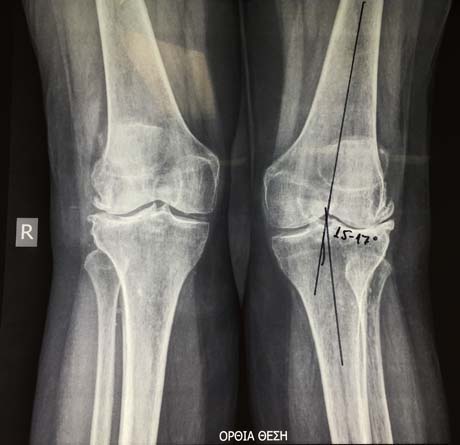

Γυναίκα 73 ετών που πάσχει από προχωρημένη οστεοαρθρίτιδα στα γόνατα ιδίως όμως αριστερά. Τα γόνατά της έχουν παραμόρφωση βλαισότητας με το αριστερό να φτάνει τις 17 περίπου μοίρες γεγονός να παύει να είναι λειτουργικό δημιουργώντας προβλήματα στη βάδιση.

Η παραμόρφωση βλαισότητας στο αριστερό γόνατο είναι φανερή ακόμα και όταν η ασθενής βρίσκεται στην υπτία θέση (ξαπλωτή).

Προεγχειρητικός ακτινολογικός έλεγχος σε όρθια θέση της ασθενούς. Η παραμόρφωση βλαισότητας στο αριστερό γόνατο ξεπερνά τις 15 μοίρες με φόρτιση των σκελών.

Μέτρηση της παραμόρφωσης της βλαισότητας κατά τον προεγχειρητικό ηλεκτρονικό σχεδιασμό της εξατομικευμένης αρθροπλαστικής γόνατος PSI. Δίχως φόρτιση του αριστερού σκέλους ξεπερνά τις 10 μοίρες.